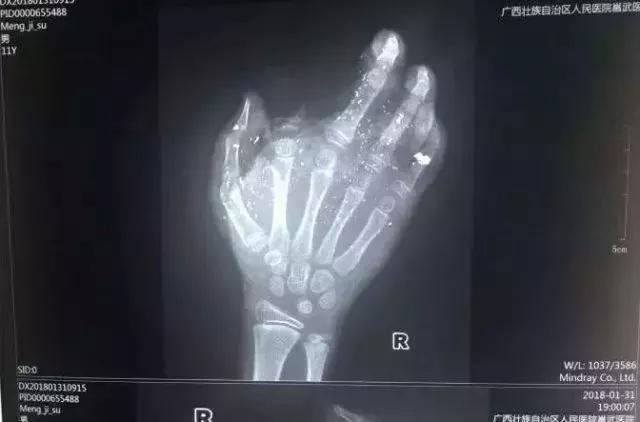

2018年1月,广西一小男孩手掌被充电的手机炸得血肉模糊,右手食指被炸没了,拇指、中指、无名指也都炸伤。